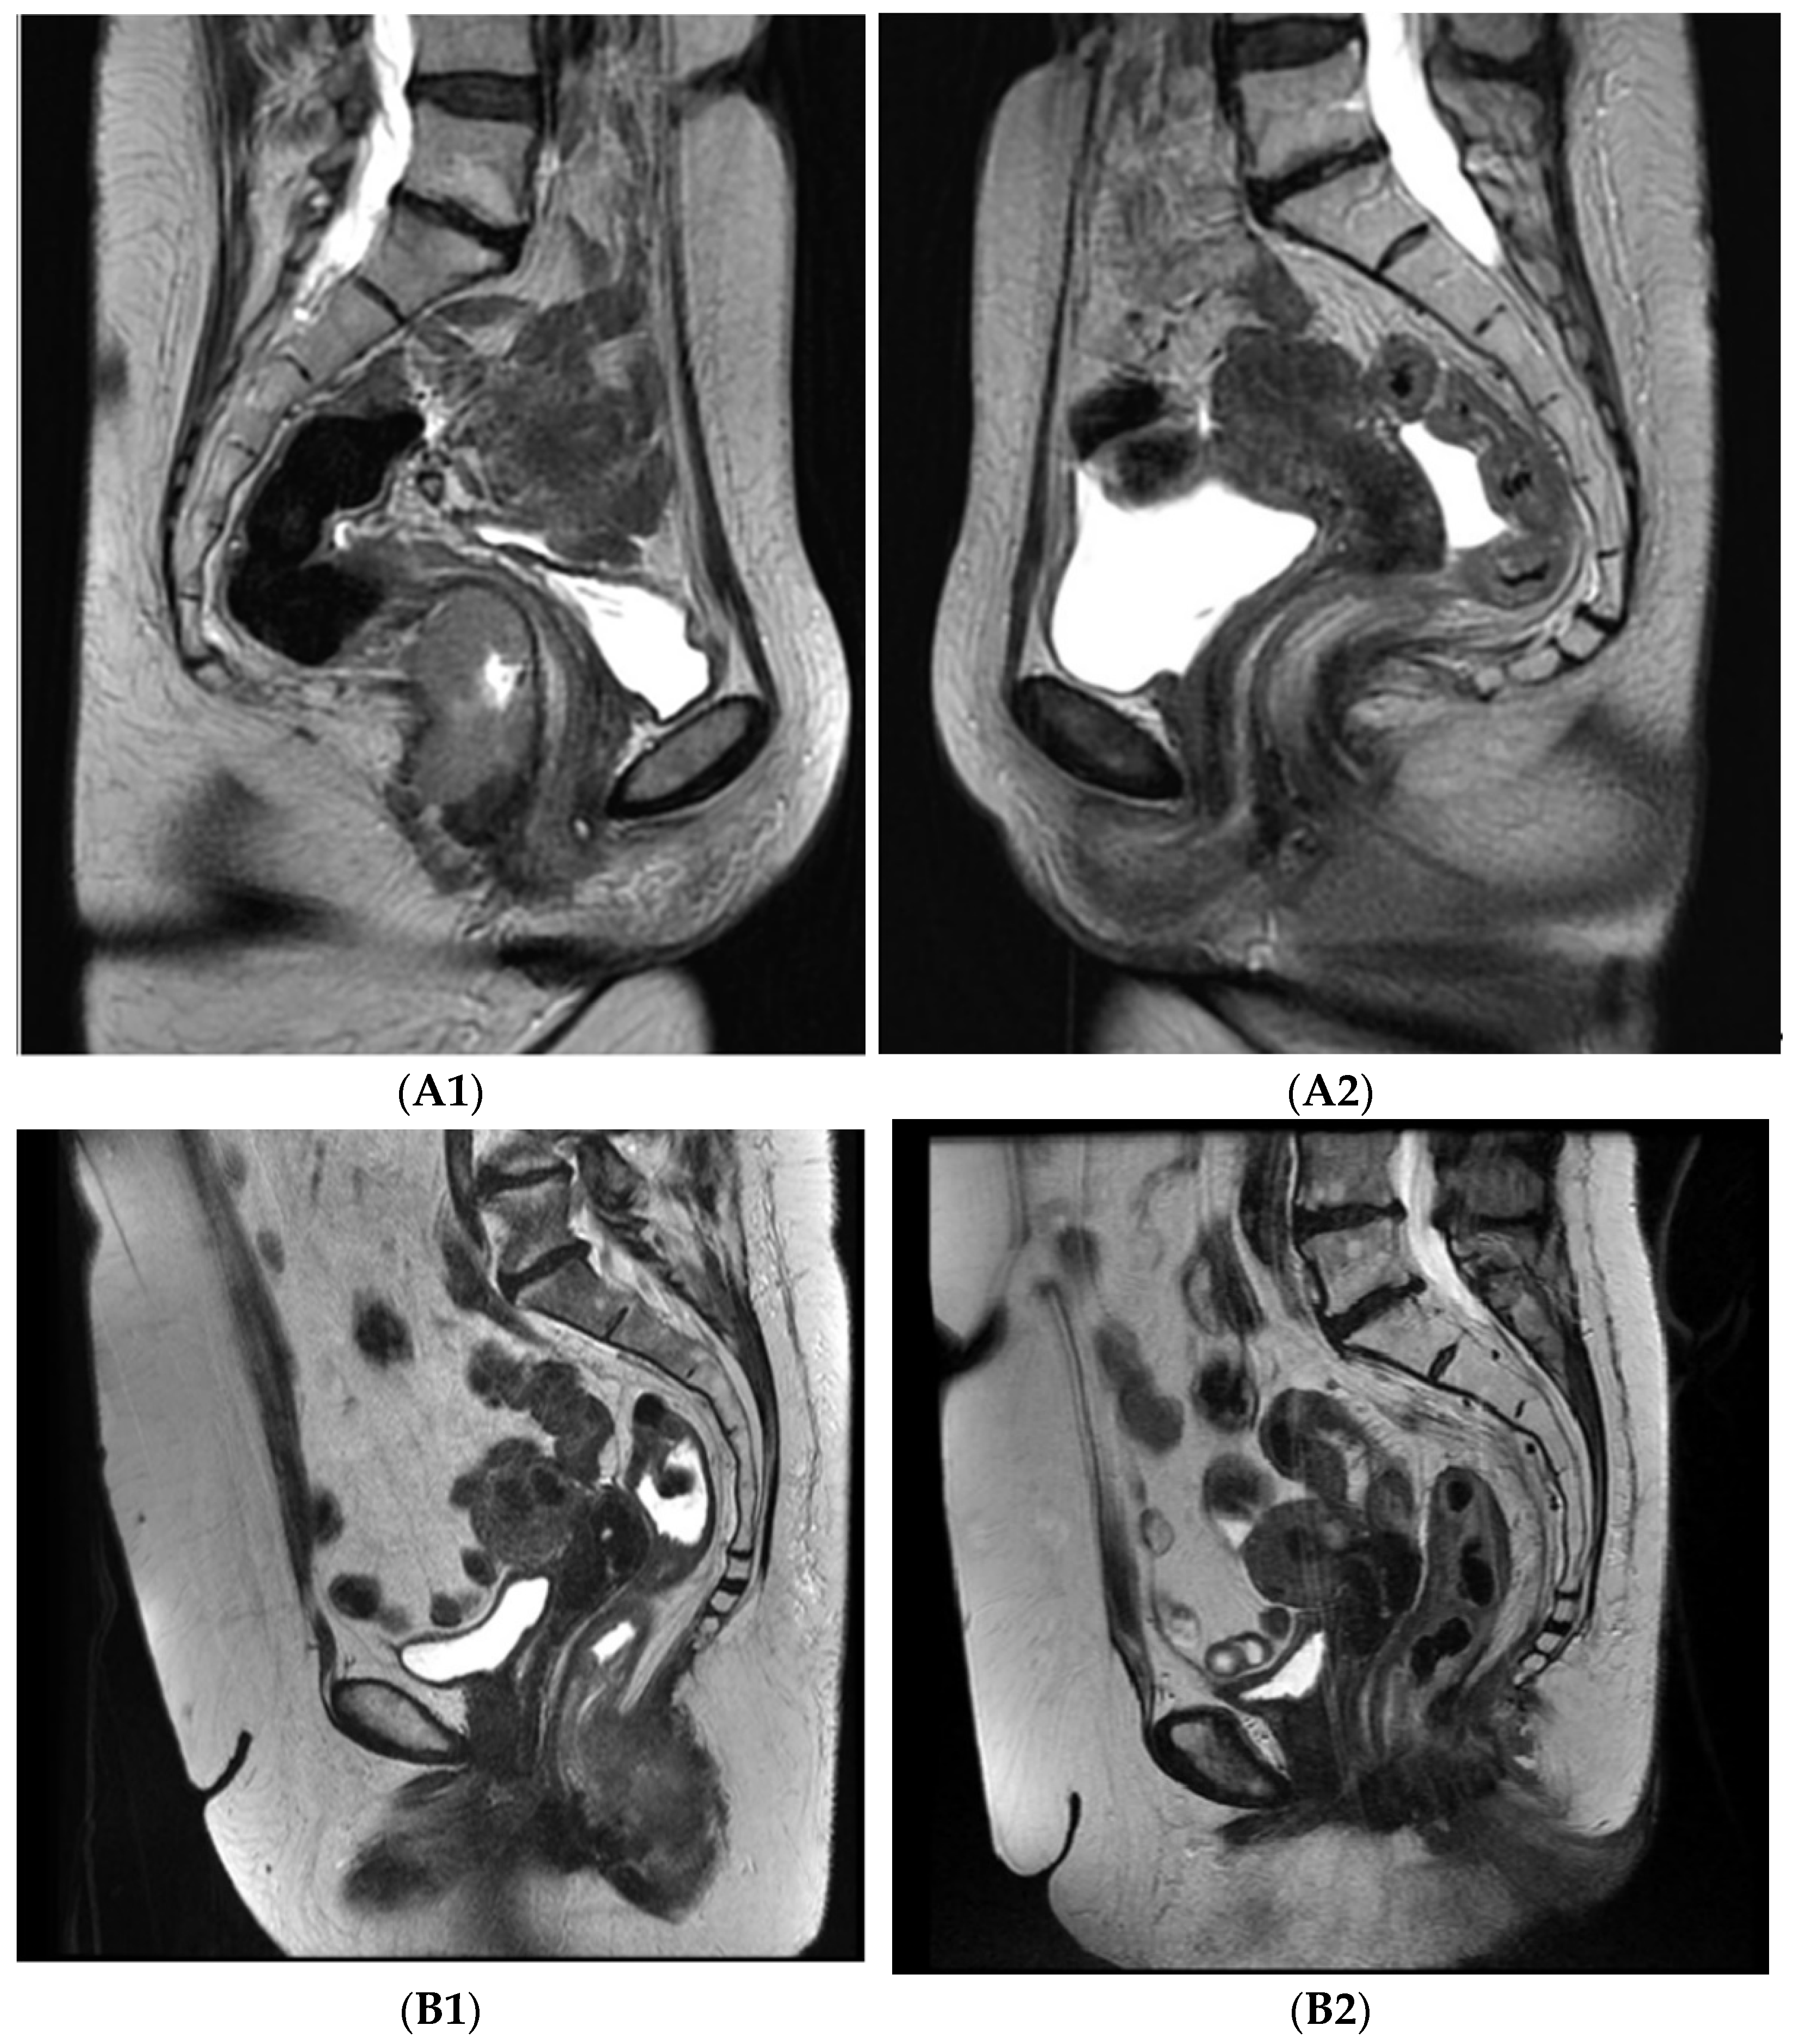

Complete regression was achieved in 36 patients (92.3%), partial regression was achieved in 2 (5.1%), and immediate progression at end of treatment occurred in 1 patient (2.6%). Both patients with partial regression apparent on radiology imaging 5 months after treatment were referred to surgery, but one patient refused radical resection and preferred follow-up (Figure 1).

Axial T2 MRI images pre- and post-treatment: A—46 years old female, stage T3N0M0, (A1) pre-treatment, (A2) 8 weeks post-treatment, complete regression; B—62 years old female, stage T3N0M0, (B1) pre-treatment, (B2) 8 weeks post-treatment, partial regression.